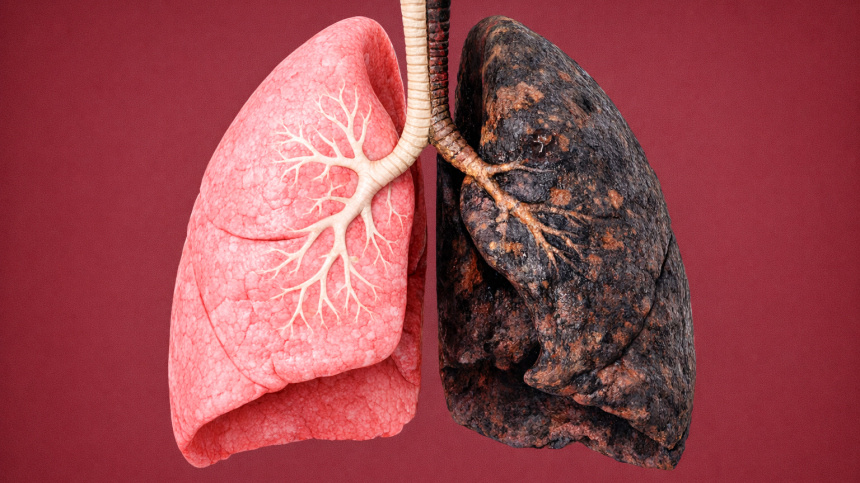

Рак легких — одно из самых распространенных и опасных онкологических заболеваний. Рак легких — одно из самых распространенных и опасных онкологических заболеваний в мире. Ежегодно оно уносит десятки тысяч жизней по всему миру, причем значительная часть случаев выявляется уже на поздних стадиях, когда шансы на успешное лечение резко снижаются. Несмотря на прогресс в диагностике и терапии, рак легких остается серьезной проблемой современной медицины. Рак легких — это злокачественное новообразование, которое развивается из клеток слизистой оболочки бронхов и легочных альвеол. Это одно из самых распространенных и смертоносных онкологических заболеваний в мире. В 2022 году в мире выявили около двух с половиной миллионов новых случаев рака легких, при этом около двух миллионов человек умерло от этого заболевания. В России ежегодно диагностируют примерно 50–60 тысяч новых случаев. Чаще всего заболевание развивается у людей старше 50 лет. Мужчины болеют в пять-семь раз чаще, чем женщины. Почти

Рак легких — одно из самых распространенных и опасных онкологических заболеваний в мире. Ежегодно оно уносит десятки тысяч жизней по всему миру, причем значительная часть случаев выявляется уже на поздних стадиях, когда шансы на успешное лечение резко снижаются. Несмотря на прогресс в диагностике и терапии, рак легких остается серьезной проблемой современной медицины.

Рак легких — это злокачественное новообразование, которое развивается из клеток слизистой оболочки бронхов и легочных альвеол. Это одно из самых распространенных и смертоносных онкологических заболеваний в мире.